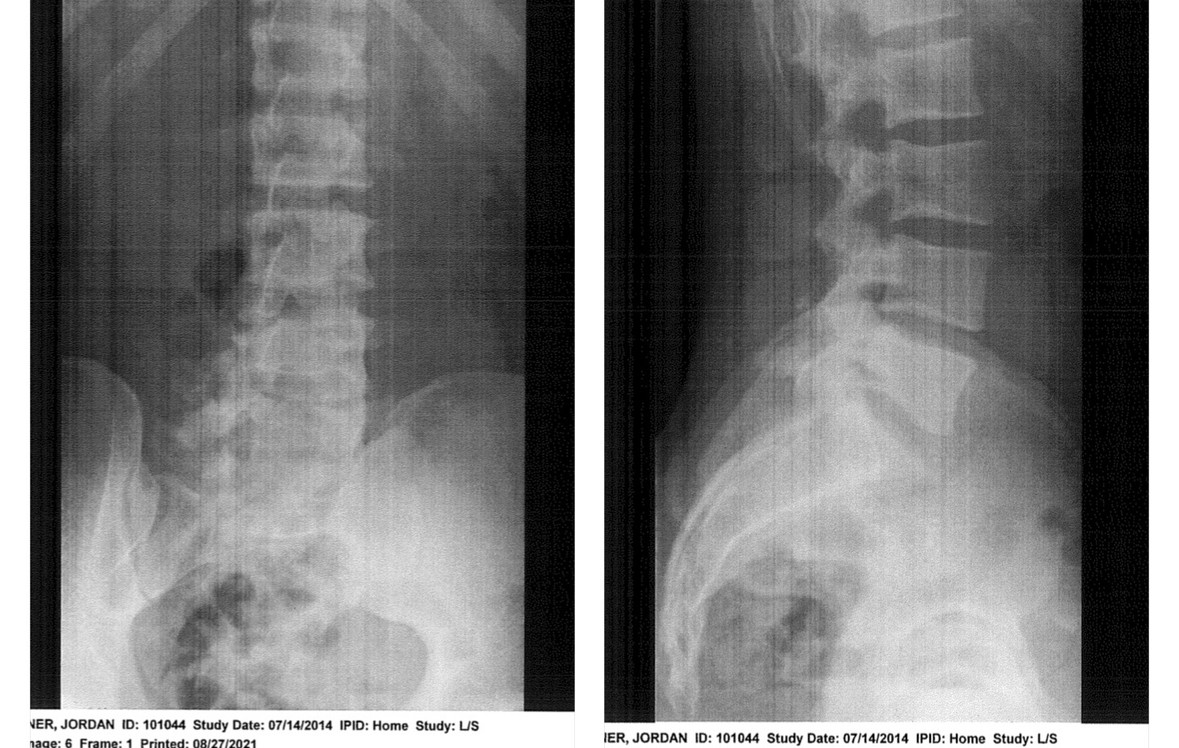

X-Rays

Posture: Posterior Pelvic Tilt

TYPE OF EXAM: Views of the sacrum and coccyx. FINDINGS: There is no fracture of the sacrum. There is volar angulation of the coccyx.

There is an increased lumbar lordosis, TART changes to the lumbar spine. L5 is rotated R.

There is hypomobility noted at the L4-L5 vertebrae and extending to the left sacroiliac joint (L SIJ)

T8-T12 hypomobility